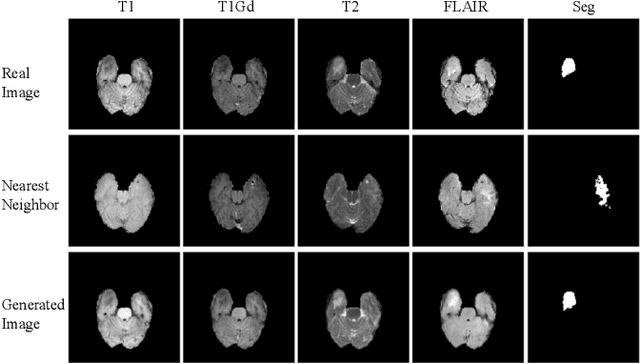

Abstract:Multi-domain data are widely leveraged in vision applications taking advantage of complementary information from different modalities, e.g., brain tumor segmentation from multi-parametric magnetic resonance imaging (MRI). However, due to possible data corruption and different imaging protocols, the availability of images for each domain could vary amongst multiple data sources in practice, which makes it challenging to build a universal model with a varied set of input data. To tackle this problem, we propose a general approach to complete the random missing domain(s) data in real applications. Specifically, we develop a novel multi-domain image completion method that utilizes a generative adversarial network (GAN) with a representational disentanglement scheme to extract shared skeleton encoding and separate flesh encoding across multiple domains. We further illustrate that the learned representation in multi-domain image completion could be leveraged for high-level tasks, e.g., segmentation, by introducing a unified framework consisting of image completion and segmentation with a shared content encoder. The experiments demonstrate consistent performance improvement on three datasets for brain tumor segmentation, prostate segmentation, and facial expression image completion respectively.